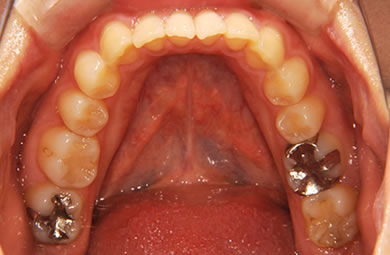

| 性別/年齢 | 女性 / 24歳 | ||||||||||||||||||||||||||||||||

| 主訴 | 矯正治療を希望し治療方針を相談する為、来院。 | ||||||||||||||||||||||||||||||||

| 治療方針 | 舌が横にはみでて、上下の歯が全く咬んでいない状態です。口元はきれいなので、歯は抜かずに歯列を少し横に広げて並べます。ゴムを使用したり、舌を訓練したりとても協力が必要な症例です。 | ||||||||||||||||||||||||||||||||

| 治療内容 | 唇側矯正(ホワイト)、保定装置 | ||||||||||||||||||||||||||||||||

| 総治療費 | 721,000円 | ||||||||||||||||||||||||||||||||

| 治療期間 | 9ヶ月 |